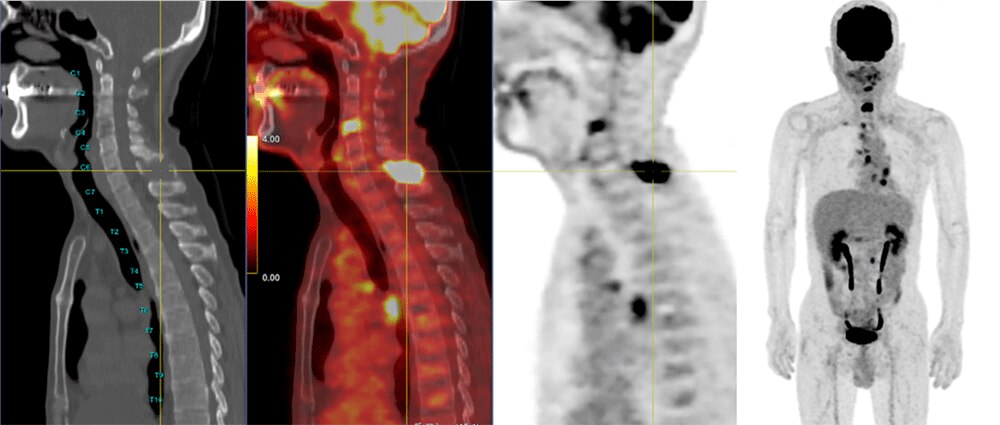

・Bone VCAR

Bone VCARとは、読み込んだCT画像から椎体の番号を自動でラベリングしてくれる機能です。椎体に圧迫骨折がある場合や異常集積がある場合に使用しています。読影レポートを作成する際に集積位置を椎体の何番目にあるかを記載することがありますので、その際に自動でラベリングする機能が役に立っています。

50代 男性 肺がん:術後腫瘍マーカー上昇のためFDG-PET検査施行

C7(SUVmax=10.28)の棘突起、C4(SUVmax=5.44)椎体等に転移あり

(写真ではわかりにくいが、左端の画像で椎体の前方にレベルが表示されている)